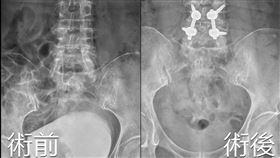

7旬嬤泌尿道發炎 靠開脊椎竟能杜後患

73歲郭阿嬤,日前因高燒送醫,檢查已有泌尿道感染以及...

2023/05/09 17:28